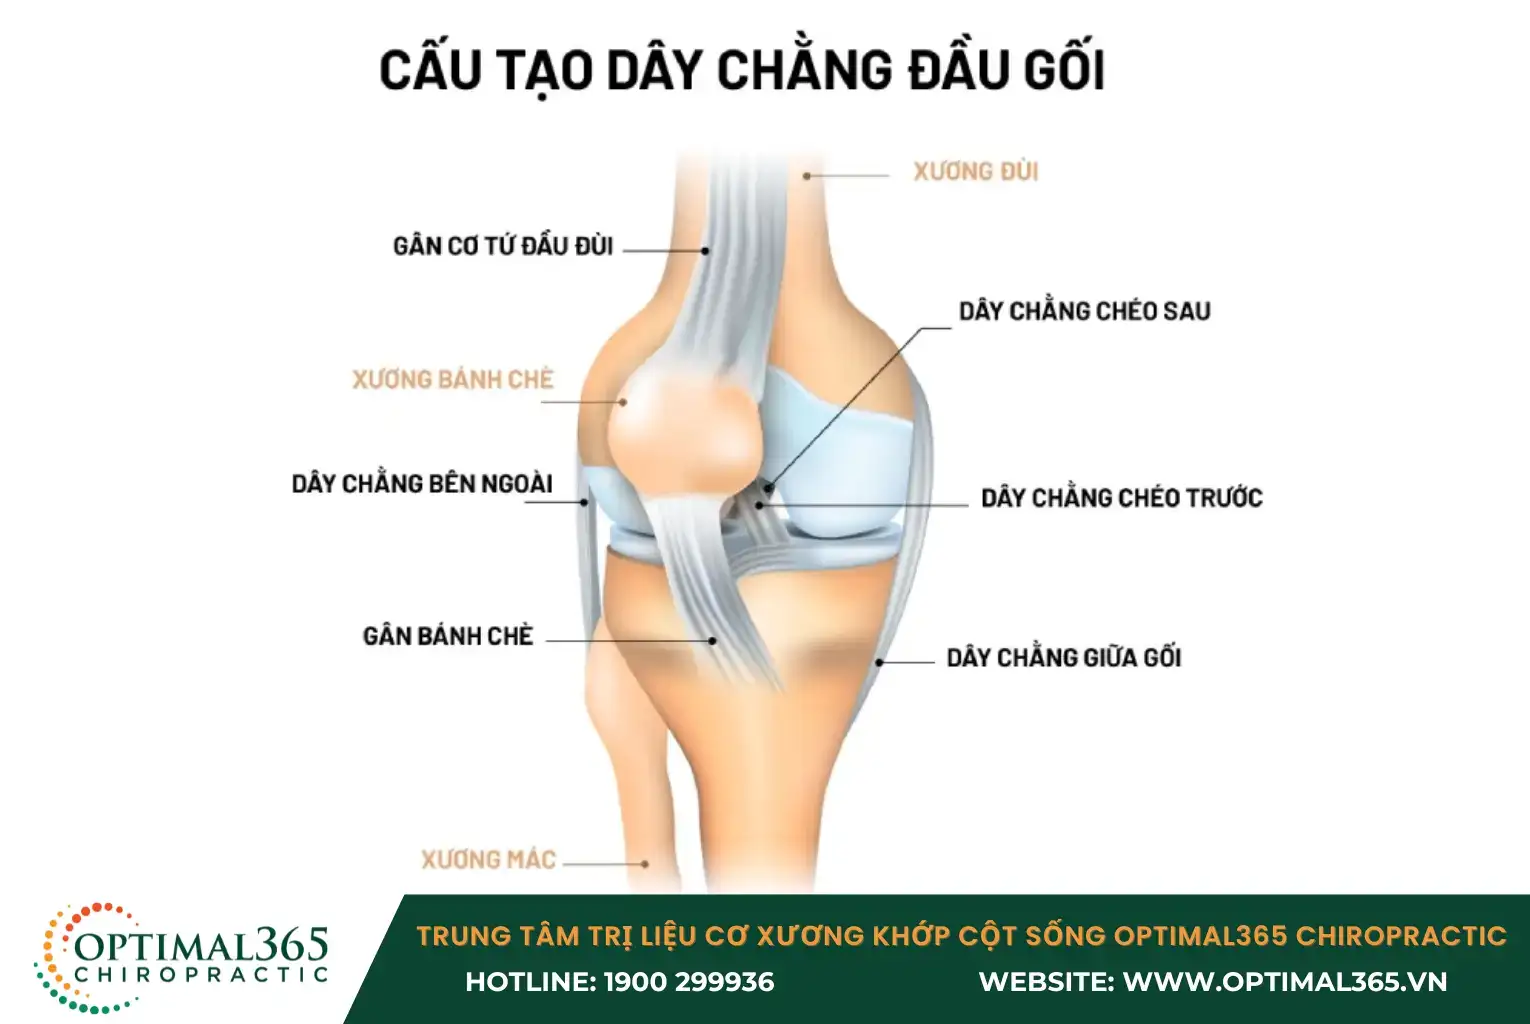

Tổng quan về cấu tạo của dây chằng đầu gối

Khớp gối là một cấu trúc phức tạp, gồm nhiều thành phần chính như xương lồi cầu đùi, mâm chày, xương bánh chè và các lớp sụn bao quanh đầu xương.

Về mặt chức năng, h ệ thống gân, cơ và dây chằng đóng vai trò quan trọng trong việc giữ cho khớp gối ổn định, có khả năng chịu lực và đàn hồi lớn, từ đó hỗ trợ các hoạt động vận động diễn ra trơn tru.

Hệ thống dây chằng của khớp gối bao gồm:

- Dây chằng chéo trước (ACL): Nằm ở trung tâm khớp gối, có vai trò kiểm soát sự chuyển động xoay và di chuyển về phía trước của xương chày, giúp khớp gối duy trì sự ổn định.

- Dây chằng chéo sau (PCL): Vị trí phía sau khớp gối, kiểm soát chuyển động lùi về sau của xương chày.

- Dây chằng giữa gối (MCL): Kéo dài từ mặt trong của đầu trên xương chày lên mặt trong của đầu dưới xương đùi, giúp ổn định mặt trong của cẳng chân.

- Dây chằng bên ngoài (LCL): Nằm ở phía ngoài của khớp gối, tạo thành một góc hẹp phía sau, có nhiệm vụ giữ vững mặt ngoài của đầu gối.